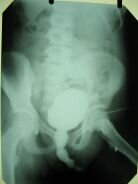

На цистограммах, выполненных во время мочеиспускания, отмечается значительное расширение мочеиспускательного канала над препятствием (рис. 1).

Рис. 1. Цистограмма больного с посттравматическим сужением мочеиспускательного канала (указано стрелкой). Отмечается значительное расширение вышележащих отделов уретры. |